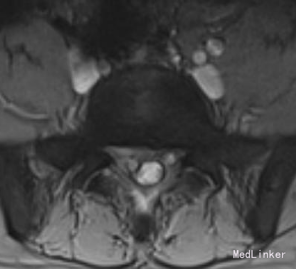

诊断:腰椎间盘突出症 (腰5/骶1髓核游离型) VAS评分:9分 ODI评分:96% 疼痛剧烈,右下肢难以伸直,坐卧不宁;给予常规脱水,激素,止痛等治疗无效;不同意手术,反复要求保守治疗。 保守治疗3天,患者疼痛仍无明显缓解,同意行手术治疗 手术方案:椎板间隙入路PELD 术后予以止痛,脱水,小剂量激素等治疗, 术后第二天:右下肢麻木疼痛明显缓解。查体:右小腿后侧及足背外侧皮肤触觉恢复;右足拇跖屈肌力4+级;右侧直腿抬高试验(-);右侧跟腱反射仍减弱。 术后第5天:出现右小腿及足底针刺样疼痛症状加重,麻木感,伴有右下肢间歇性抽搐,次数较频繁,以夜间为甚。查体:腰椎活动无明显受限,右小腿后面及右足背外侧触痛明显;双下肢屈伸肌力、肌张力基本正常;右侧直腿抬高试验(-),右侧跟腱反射仍减弱。 予以加大NSAID及地米治疗,效果不明显,夜间疼痛难以入睡。复查腰椎MRI,未见髓核再脱出,减压彻底 诊断:考虑右侧骶1神经根神经病理性疼痛 治疗: 普瑞巴林 75mg Bid;神经妥乐平 2# Bid; 阿米替林 25mg Bid 外加神经营养治疗 治疗1周后,症状明显缓解